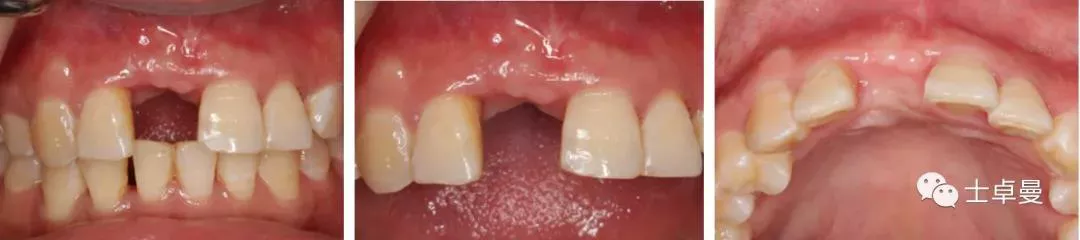

▷ 种植牙前检查(牙周系统治疗3个月后)口内检查

·      11缺失,拔牙创愈合良好,12松(Ⅰ-Ⅱ),21松(Ⅰ-Ⅱ),22松(Ⅱ),余留牙未见异常;

·      咬合正常,低位笑线,中厚龈生物型;

·      全口卫生状况良好,无牙结石。

·       使用SAC工具评估该患者属于美学中风险,告知患者12、21、22牙槽嵴均有明显吸收,且12松(Ⅰ-Ⅱ),21松(Ⅰ-Ⅱ),22松(Ⅱ);

·       根据口腔种植临床指南中对垂直骨增量方案的描述,缺牙区骨增量的效果与邻牙牙槽嵴高度及邻牙牙周状况有关,如仅进行11区的垂直骨增量,后期修复效果可能不佳,但患者考虑后要求仅对11进行种植修复,并同意行颏部自体骨移植+延期种植修复的方案。